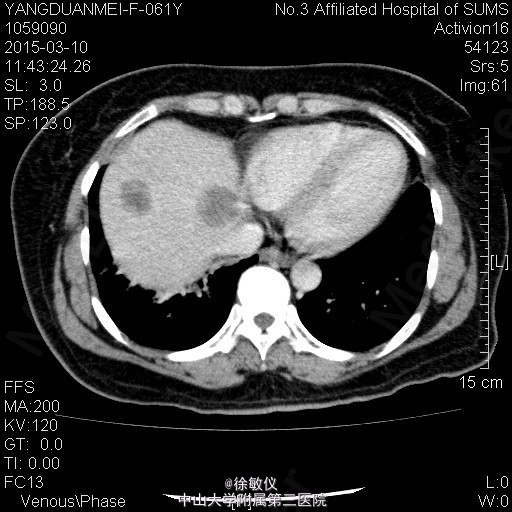

老年女性,主诉:咳嗽2月,胸部CT发现中央型肺癌1天。 现病史:患者2月前无明显诱因出现咳嗽伴胸闷气促,伴少量白色粘液痰,无痰中带血、咯血等不适,当时自行服用“消炎药”治疗(具体不详),2月来症状逐渐加重,至当地医院就诊,查胸部CT提示:右侧中央型肺癌并纵隔淋巴结转移,肝脏考虑转移灶。现为求进一步治疗入院。近期体重减轻2斤。 查体:生命体征平稳,全身浅表淋巴结未扪及肿大。心肺腹查体无特殊。 胸部CT:1、右下中央型肺癌,并右肺门及纵隔多发淋巴结转移;右中间段支气管、中下叶支气管狭窄、闭塞,右肺阻塞性炎症,考虑右侧肺动脉、右下肺静脉受侵。2、肝S4、S8转移瘤。 诊断: 右侧中央型肺癌并肝转移。